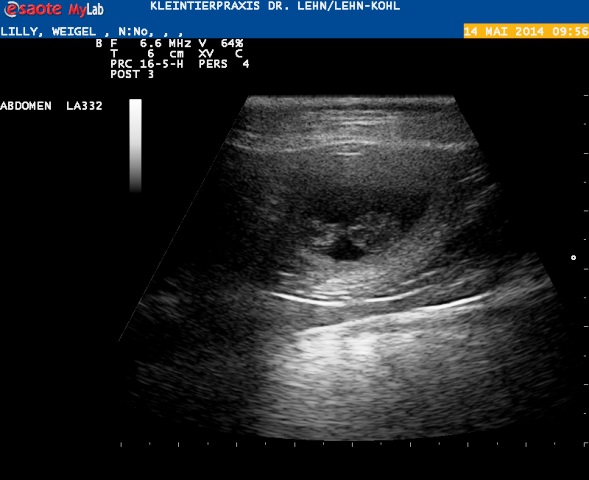

Wir mussten den Ultraschall auf heute verschieben :) hier kommen die ersten Fotos der H-ummelchen :)

Hier auch die Fruchtblase und ein anderes H-ummelchen :) :)

Leider kann man nicht sehen wie viele es sind, diese Überraschung bereitet Lilli uns erst bei der Geburt!!